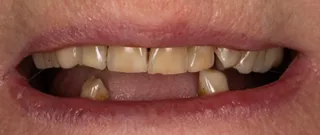

2a. View of the mouth showing limited gingival exposure.

2a